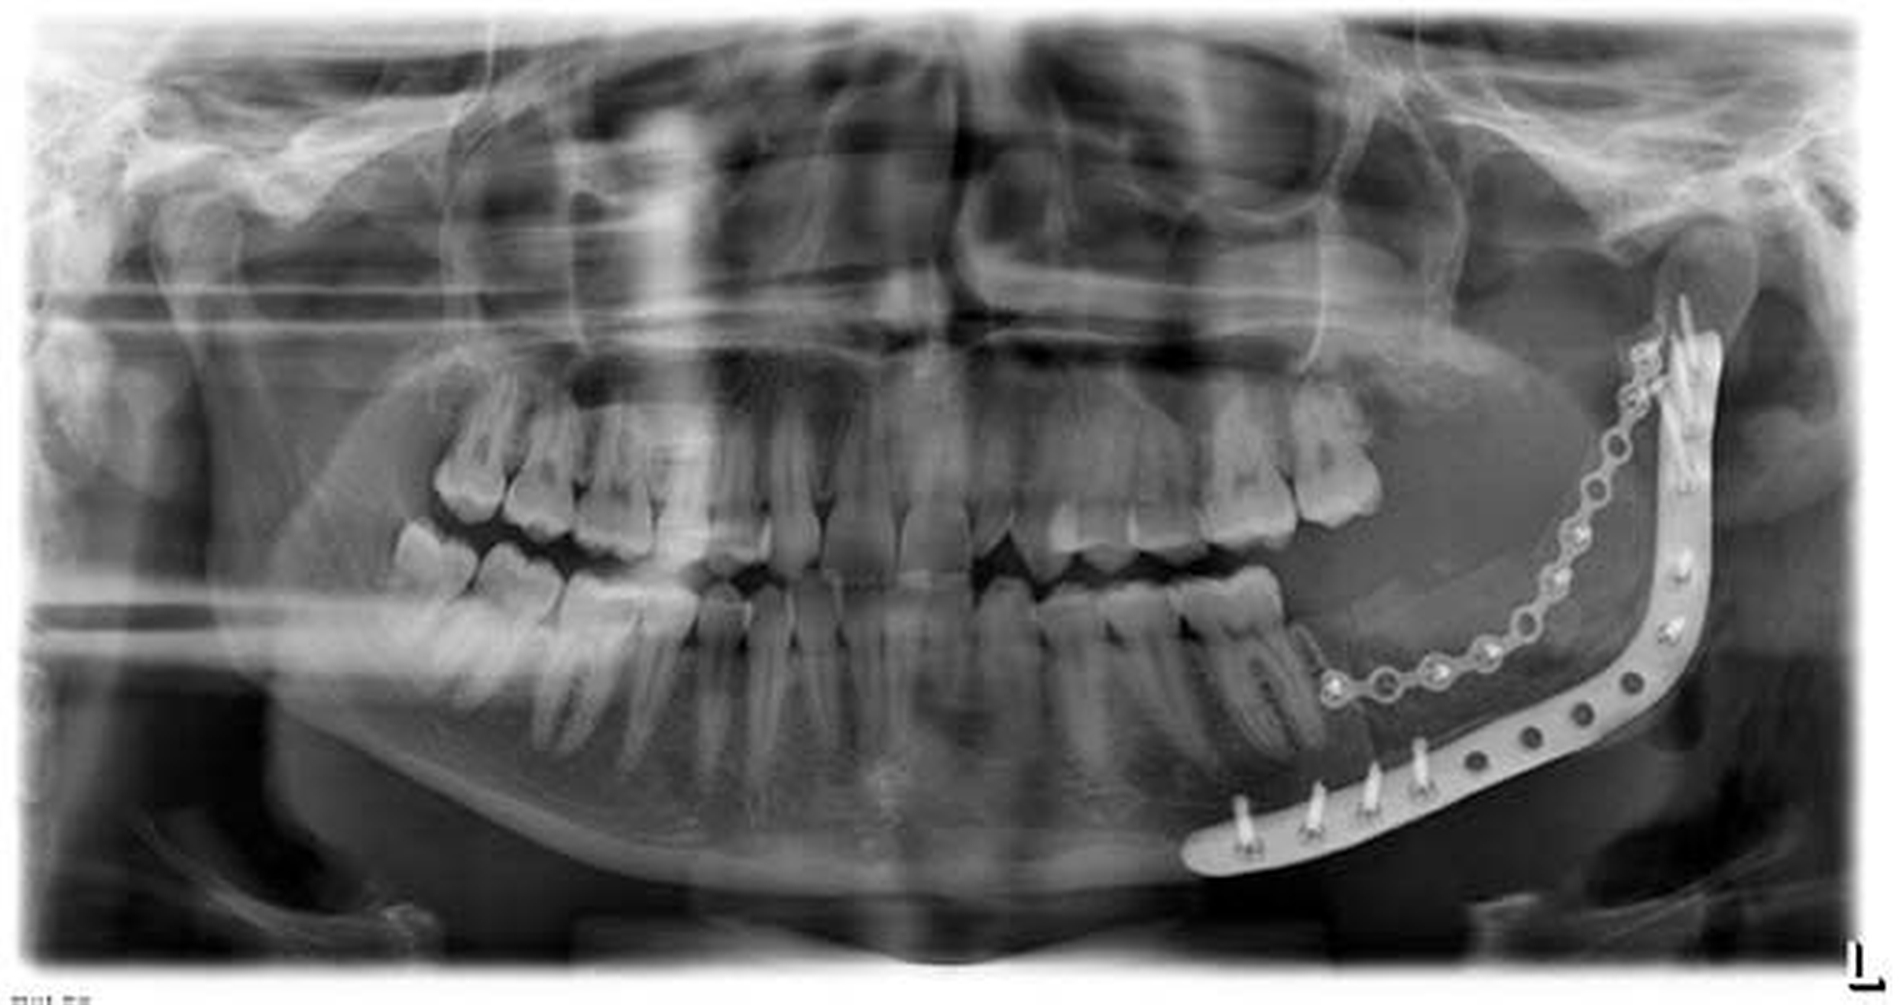

Eine 23-jährige Patientin stellte sich bei einem zunehmenden Druckgefühl im Kieferwinkel links in unserem Klinikum vor. Klinisch imponierten intraoral lediglich Verbreiterungen der Mandibula in regio 38 sowie des Ramus ascendens links. Der N. alveolaris inf. zeigte eine regelrechte Funktion. Eine faziale Asymmetrie bestand nicht. Es erfolgte die Anfertigung eines Orthopantomogramms (Abbildung 1), das eine ausgedehnte Verschattung im Kieferwinkel links zeigte. Da es keine älteren Röntgenaufnahmen dieser Region gab, konnten keine Aussagen über den Wachstumszeitraum der Raumforderung getroffen werden.

Der N. alveolaris inf. wurde zurück in sein ursprüngliches Bett verlagert und mit Fibrinkleber bedeckt. Nun erst wurde die Rekonstruktionsosteosyntheseplatte eingebracht und entsprechend der Planung verschraubt. Zur Augmentation des resektionsbedingten Knochenverlusts erfolgte die Transplantation zweier kortikospongiöser Beckenkammspäne von der rechten Spina iliaca anterior in den Defekt. Die Knochenblöcke wurden mit einer konventionellen Osteosyntheseplatte fixiert (Abbildung 6).